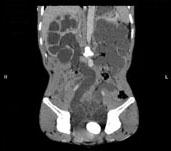

问题 男,33岁,反复尿频,尿急,尿痛3年余,排尿困难4个月,尿常规:蛋白(+),红细胞01/HP,白细胞(++),CT扫描图,下列诊断哪项说法正确 ( )

选项 A、双侧肾积水,双侧输尿管扩张 B、膀胱多发性假性憩室 C、膀胱慢性炎性肉芽肿 D、膀胱癌 E、膀胱结石

答案 ABCE